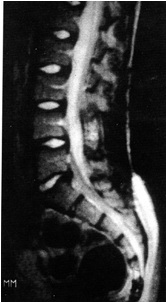

MRI and CT showed fluid in the bone (Figure. 2). Arthroscopic curettage without bone grafting was performed. A 6-mm skin incision was used to aspirate the bloody fluid and remove the cyst membrane (Figure 3). Pathologic examination demonstrated the cyst to be an ABC (Figure. 4). Curettage was performed using the arthroscope. Range of motion exercices were begun on the first postoperative day. The outcome was good and there was no evidence of recurrence at the 20-month follow-up (Figure. 5).

Figure 2: MRI and CT before surgery showing osteolysis and fluid in the bone.

Figure 5: MRI 20 months after surgery showing good bone formation.